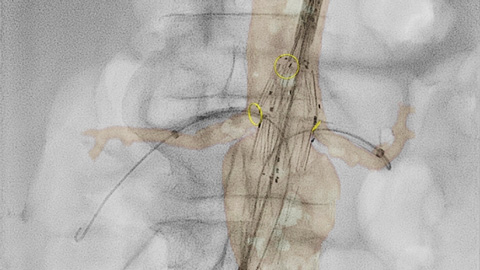

The latest version of Azurion brings great benefits to image-guided surgery such as simpler and more flexible image-guided workflow controlled from table side and SmartCT to easily adopt 3D imaging in your procedures.

Philips Azurion with FlexArm offers exceptional flexibility for image-guided surgical procedures in a sterile OR environment. FlexArm clears the room for free positioning of staff and facilitates full patient coverage with symmetrical access on both sides of the table. The imaging system can be easily re-positioned for different procedures, or completely moved away from the table. FlexArm achieved an exceptional score of 92 out of 100 on the System Usability Scale (SUS), a scientifically proven independent scale on which technological systems score 68 on average. The latest version of Azurion further supports a seamless user experience in an advanced Hybrid OR, for example by simplifying positioning with full system automatic position control.

The enhanced touch screen module (TSM) allows you to fluidly control a comprehensive range of multi-modality interventional tools, including SmartCT’s advanced 3D visualization and measurement, IntraSight’s plug-and-play digital IVUS and other compatible procedure-specific tools within the sterile field. This reduces interactions and the need to walk back and forth between different consoles and the control room to launch an application or perform a measurement during minimally invasive procedures, thereby reducing sterility breaks.

We offer a range of advanced clinical tools such as VesselNavigator, EchoNavigator and HeartNavigator for live 3D image guidance. Our exclusive Dynamic Coronary Roadmap helps you navigate tortuous arteries efficiently and precisely. Each surgical discipline can benefit from advanced image fusion tools that can enhance confidence, efficiency and precision during procedures.